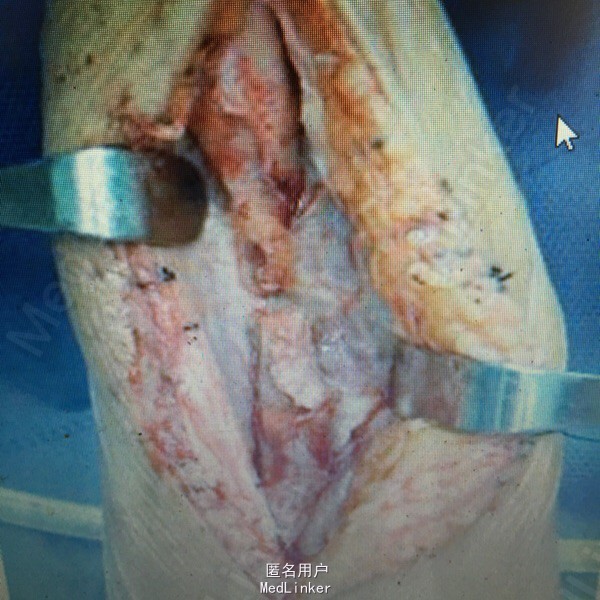

女性患者,43岁,因交通伤致右尺桡骨开放性骨折,当地医院行清创、骨折切开复位内固定术,术后尺侧切口反复红肿、流脓,经换药治疗4个月前臂仍疼痛、畸形、功能受限,X线片(A, B);第1阶段手术探查明确诊断(感染范围、程度及细菌种类),桡骨重新复位、内固定、恢复力线、间接稳定尺骨,尺骨骨折断端清创、抗生素骨水泥占位器置入(C),术后X线片(D, E);全身及局部应用敏感抗生素;第2阶段膜诱导技术修复骨缺损;切开诱导生成的生物膜,取出骨水泥占位器,钢板固定骨折(F, G);髋臼锉取骨技术获取粉碎松质骨、皮质骨混合颗粒,锁定钛板内固定和愈合片子(H, I)

具体实施膜诱导技术大体分2个阶段,第1阶段:静脉应用抗生素,清创手术时于骨缺损区填充快捷式抗感染占位器,塑形并连接骨折断端维持局部稳定性;第2阶段:在第1次手术后6~8周,软组织愈合良好且感染控制的情况下,去除填充的占位器,并保留自体诱导形成的膜结构(1~2 mm厚的筋膜样结构),然后在膜内填充碎颗粒状自体松质骨。其基本原理是通过在骨缺损处置入骨水泥占位器诱发机体异物反应,形成诱导膜结构,二期在诱导形成的膜结构内行自体松质骨颗粒或人工骨颗粒植骨,诱导形成的膜结构将移植骨与周围环境相隔离,为骨修复创造了一个相对封闭的生物学环境,在阻隔其他组织(如纤维瘢痕组织)长入缺损区的同时能够为骨修复提供丰富的血供、成骨因子。其优点是:技术操作简单、骨缺损修复快、愈合时间与骨缺损长度无关、供区并发症少等。这种模式也许是未来治疗感染性骨缺损的一种趋势。